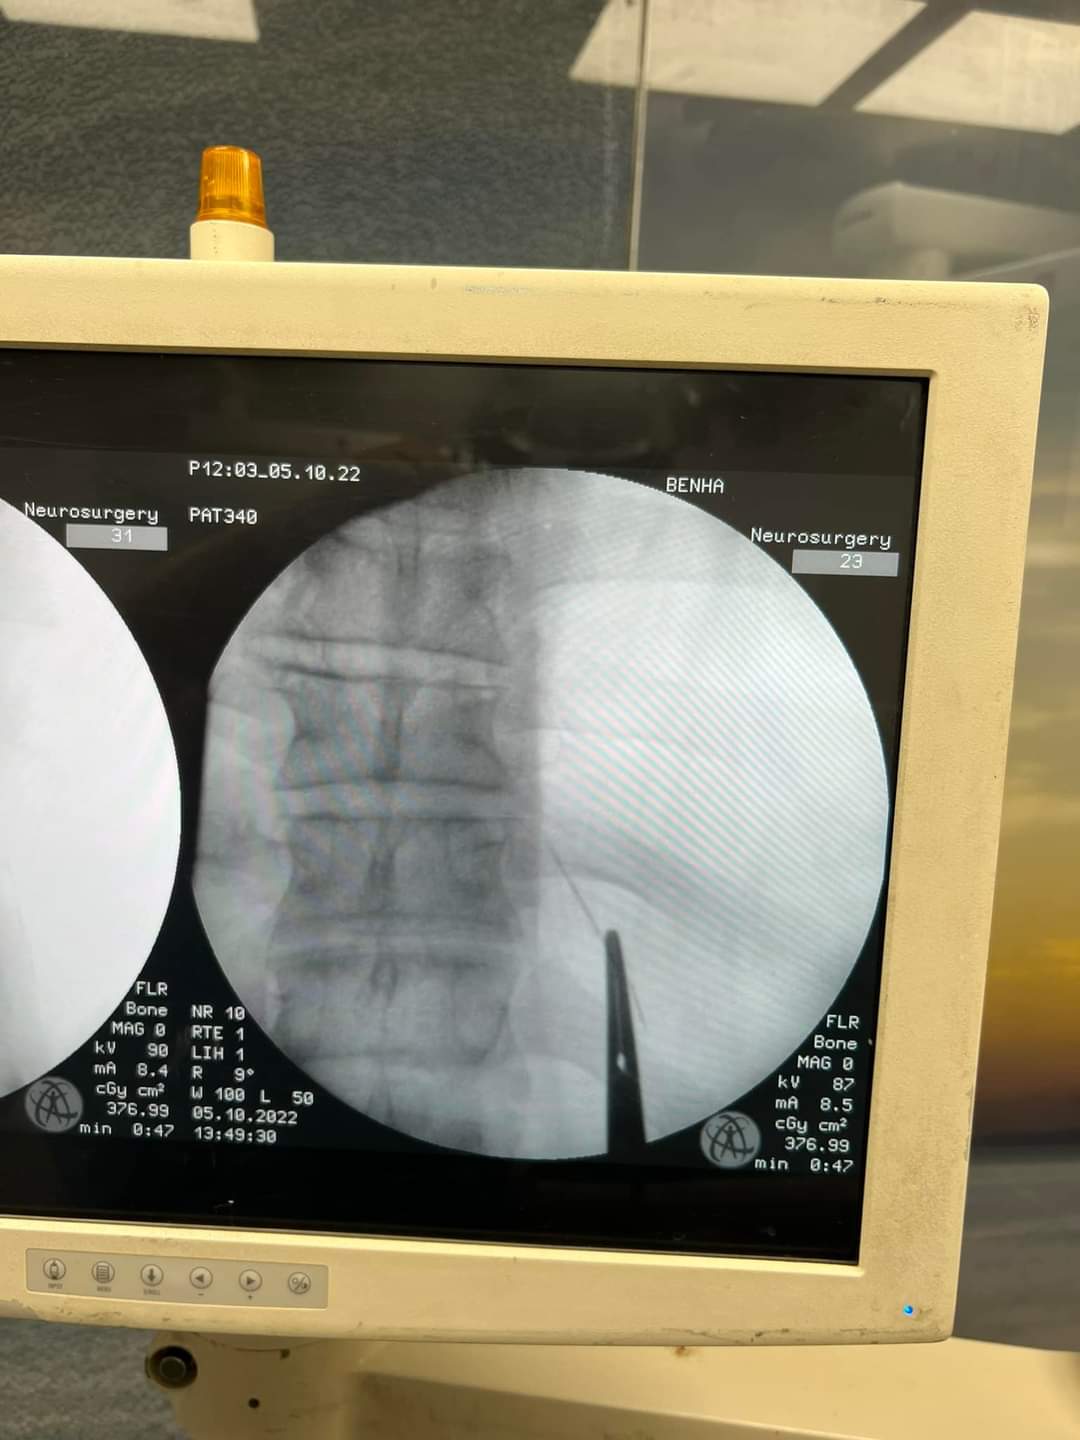

وأوضح البيان أنه تم حجز المريض بالقسم وتجهيزه لعملية سريعة، تم فيها الاستعانة بجهاز الأشعة الملحق بغرف العمليات (C-arm)، حيث تم تحديد مكان الإبرة والفتح الجراحي عليها مباشرة، واستخراجها بنجاح، ولكن على هيئة قطع منكسرة بسبب الصدأ، نظرا لبقائها طوال هذه المدة.

وقالت إدارة المستشفى، في بيان لها، إنه تم إجراء عملية فتح جراحي صغير 3 سم، لاستخراج إبرة تنجيد، دخلت بطريق الخطأ في ظهر مريض خلف القفص الصدري مباشرة، حيث تركها المريض لمدة عامين خوفا من إجراء العملية.